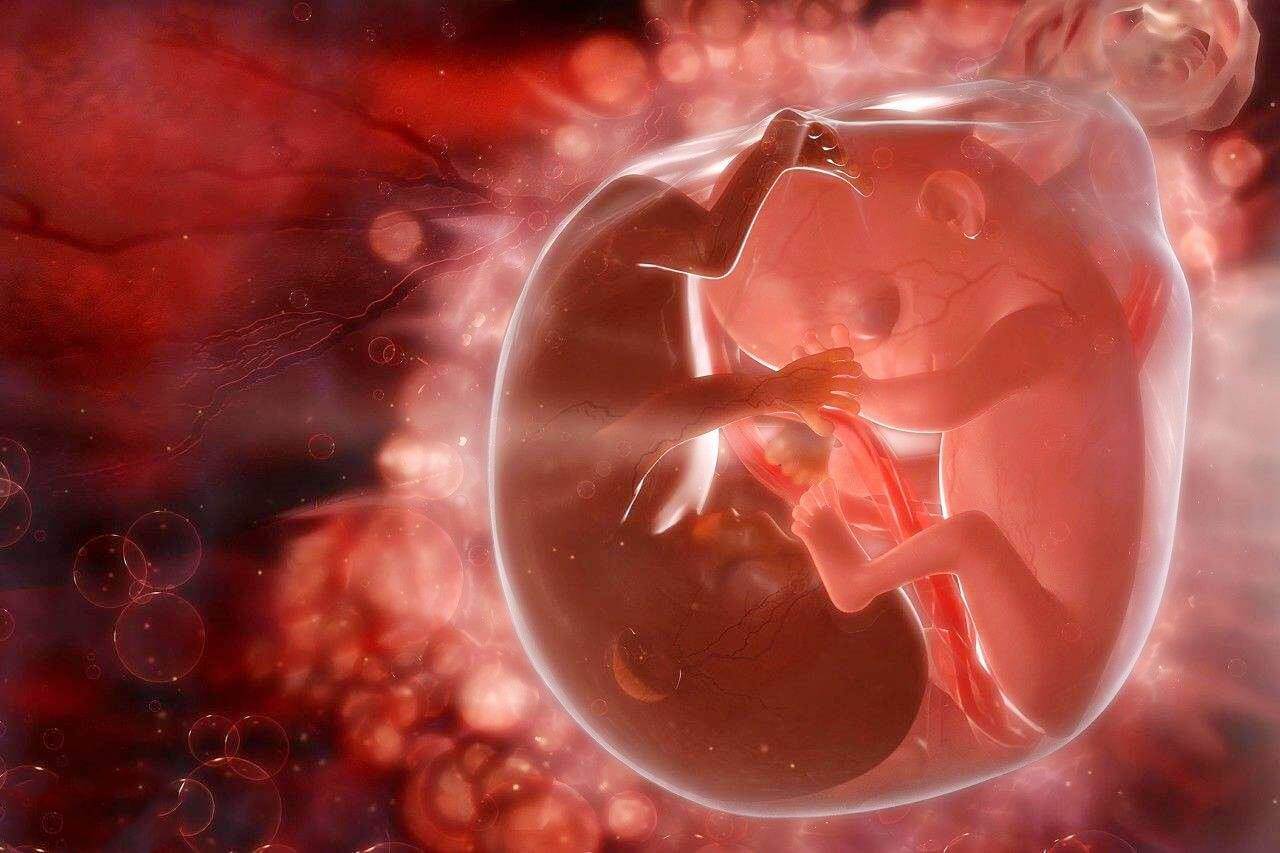

試管養囊和不養囊的區別主要在於養囊可以提高移植的成功率,養囊在一定程度上可以讓自己的受精卵發育的更好,從而提高試管嬰兒的移植率。在養囊的過程中,由於受精卵為男孩,囊胚生長力比較旺盛,發育的早也快,這就是為什麼囊胚很多是兒子。

對於試管助孕的女性朋友而言,好不容易熬到成功移植了,移植後的心情既充滿著期待心裡也會有所焦慮,畢竟沒有得等到成功著床的好訊息,也並不能代表著真正意義上的成功。一般情況下來講試管嬰兒移植囊胚的成功率是相當高的,尤其是移植等級比較高的優質囊胚的成功率會更高。但女性朋友們也會聽說優質囊胚也會出現晚著床的情況,這是什麼原因呢?今天來給大家進行相關講解。優質囊胚為什麼會晚著床首先我們來了解一下囊胚著床的全過...